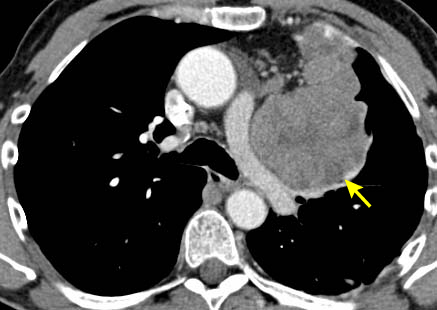

Tomografia computadorizada (TC) do tórax mostrando timoma em estádio III de Masaoka-Koga com comprometimento da parede torácica anterior e invasão da região medial do pulmão esquerdo

Do acervo de Cameron Wright, MD; usado com permissão